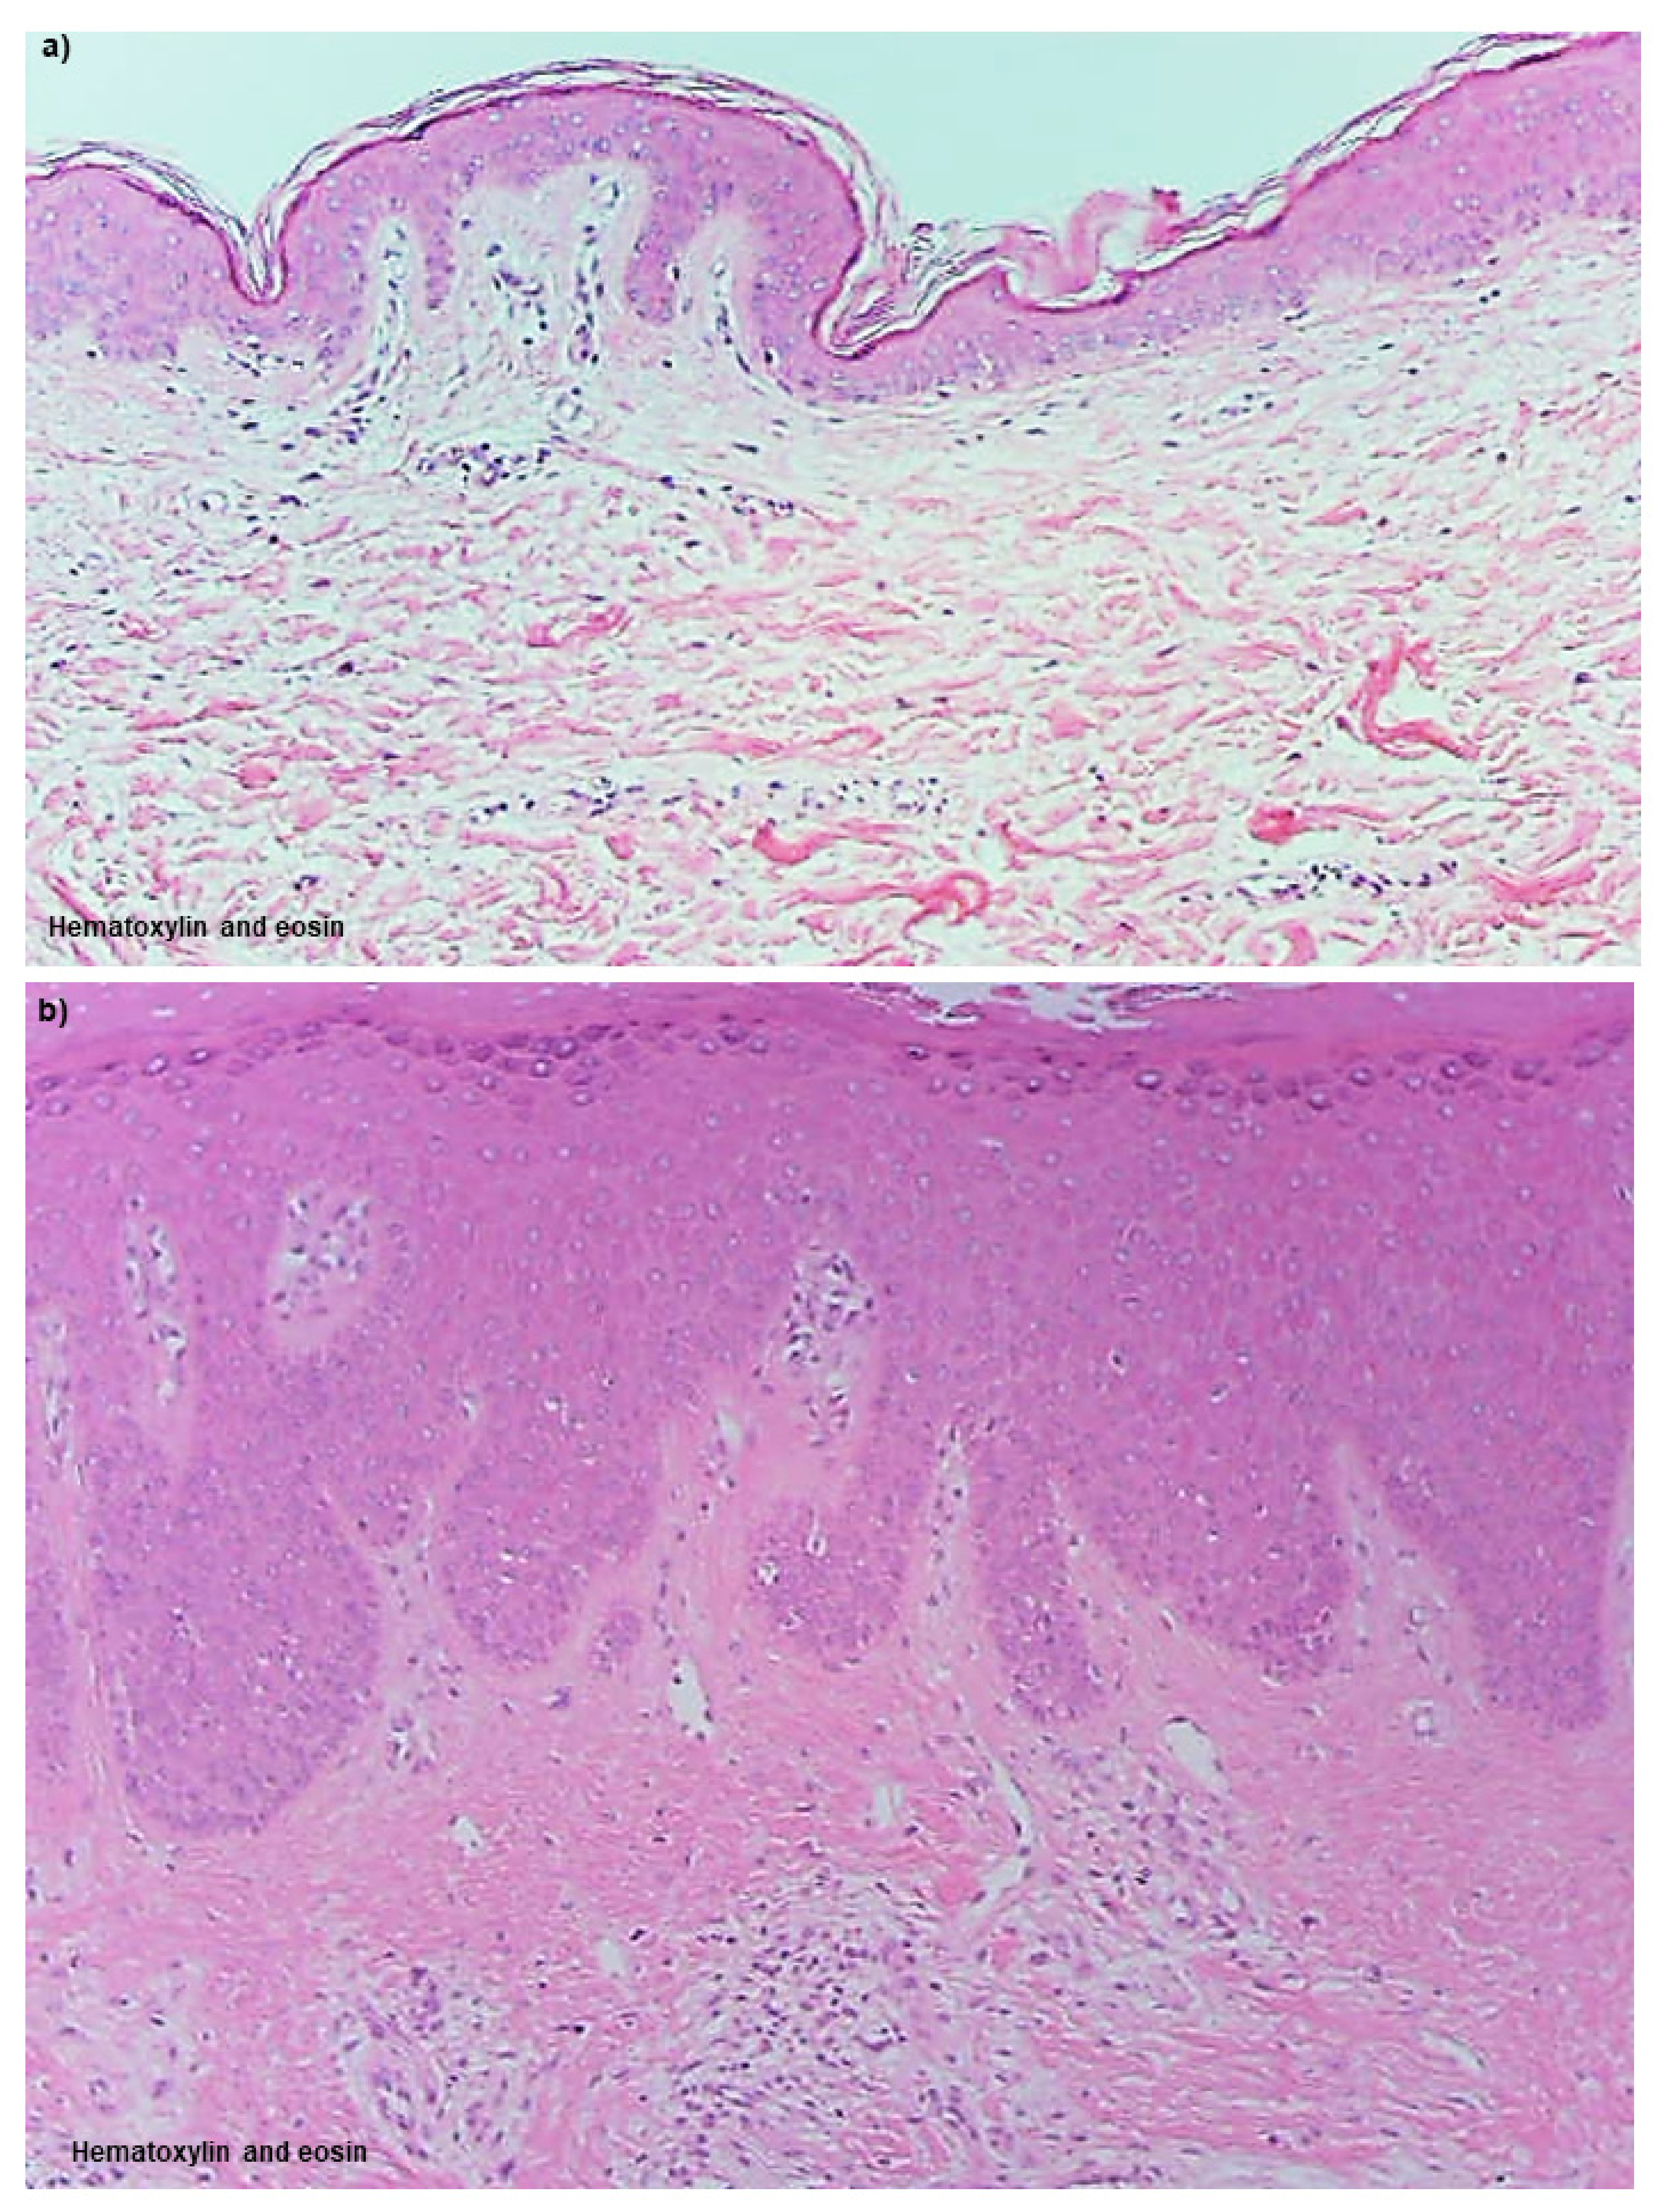

Uninvolved Skin

Non-Spongiotic Areas of Lichenified Eczema

Spongiotic Dermatitis in APT Positive-Reaction Sites

Spongiotic Dermatitis in Lichenified Eczema